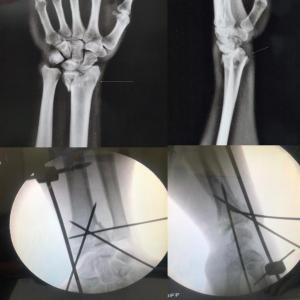

Complex trauma Surgeries